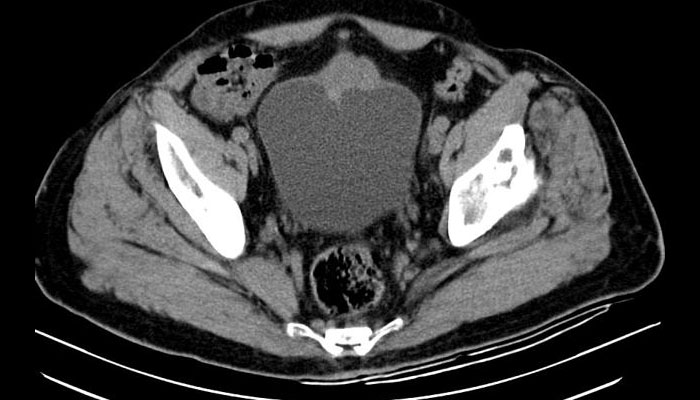

Hình ảnh khối u tăng sinh không đồng nhất nằm ở thành trước bàng quang, lan vào bên trong bàng quang, với dấu hiệu lan vào phần còn sót lại của ống niệu rốn.

6.2. CT scan / MRI

Dùng khi nghi ngờ áp-xe hoặc đánh giá cấu trúc rõ hơn.